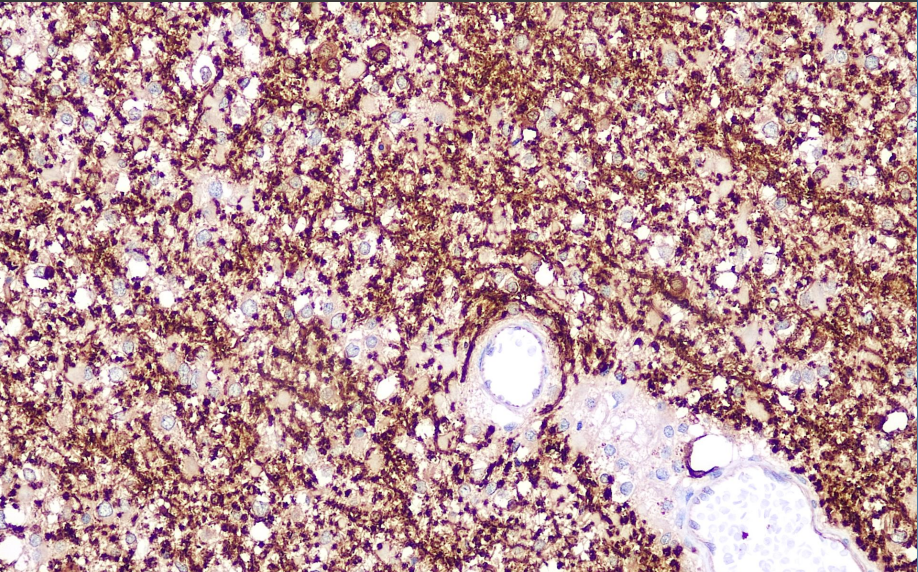

Positive control: brain

Myelin basic protein (MBP) is the main component of myelin structural proteins and is distributed in the central and peripheral nervous systems. The main markers are soft tissue tumors, acoustic neuromas, neurofibromas and neurosarcomas, but it shows a negative reaction in other spindle cell tumors, melanocytes and tumors of their origin.

MBP antibody reagents can specifically bind to MBP molecular antigens. Immunohistochemical kits containing MBP antibody reagents are suitable for the auxiliary diagnosis of demyelinating diseases of the central nervous system.